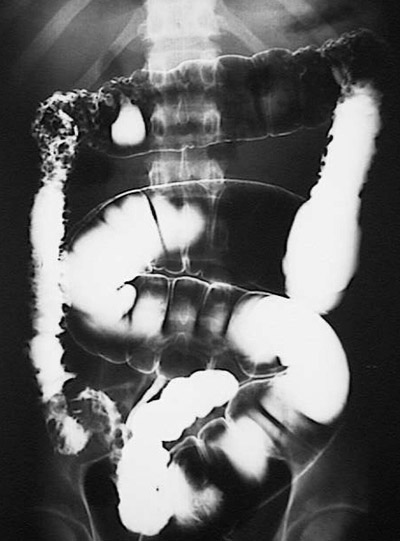

| The barium enema shown here reveal involvement of the colon with Crohn's disease. Note that the area of transmural inflammation with thickening of the wall and narrowing of the lumen is in the ascending colon, having skipped the area from rectum to the transverse colon. |